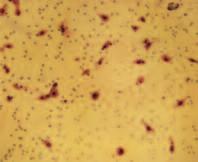

Immagine al microscopio di cellule leucemiche. Le sfere rosse del pacmen rappresentano gli enzimi collagenasi.

La foto nella pagina a fianco mostra una sezione trasversale al microscopio del fegato di un paziente con ‘leucemia linfatica’. Ciascuno dei piccoli puntini viola nella foto è un globulo bianco (in questo caso linfocita) che ha invaso il tessuto del fegato (aree rosa).

Considerando l’enorme quantità di questi puntini viola e il numero di enzimi che assimilano il collagene che ciascuno produce, è facile prevedere l’ingente distruzione del tessuto connettivo e il danno apportato all’organo da questo tipo di cancro.

Immagine al microscopio della leucemia linfatica

Globuli bianchi affetti di cancro (linfociti) invadono il fegato L’enorme quantità di collagenasi prodotte da queste cellule distruggono l’organo e causano insufficienza epatica.